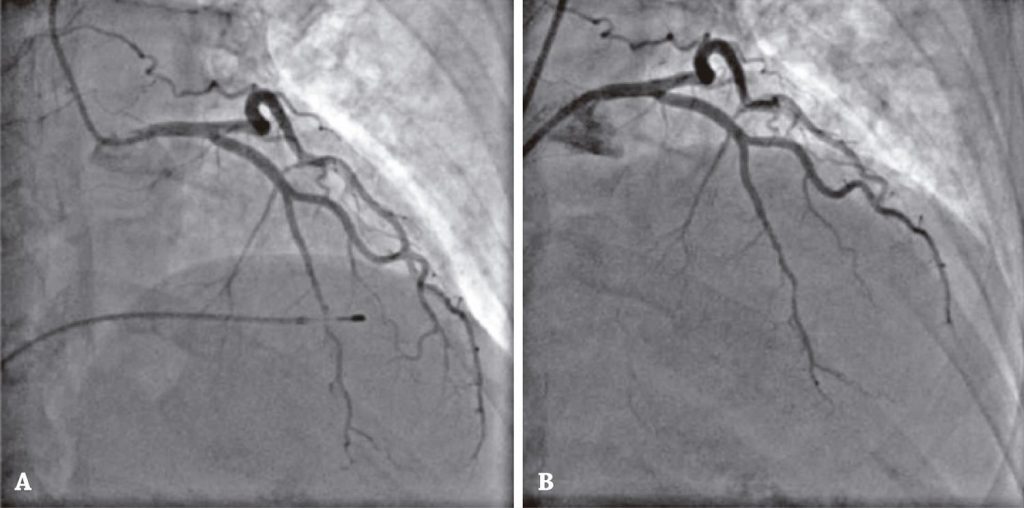

She was admitted to the coronary unit, evolved with complaint of dizziness, being identified again a second-grade 2:1 AV nodal block, and a provisional pacemaker implantation was indicated. From then on, after brachial vein access provisional pacemaker implantation, the patient developed chest pain and increased levels of ultra-sensitive troponin (305ng/mL; 12,529ng/mL; 3,525ng/mL; 1,158ng/mL; upper reference value of 60.00ng/mL).